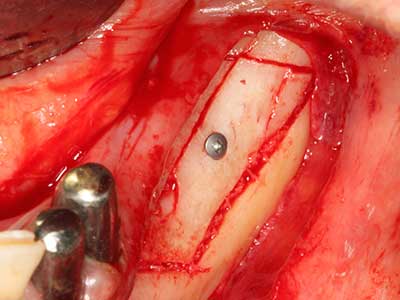

Knochengewebe ist nicht nur rein mineralisch, sondern auch in wesentlichen Anteilen aus Kollagenfasern aufgebaut. Dies gewährleistet neben einer guten Druckfestigkeit eine gewisse Flexibilität, welche für die Durchführung von Augmentationen genutzt werden kann. Bei der klassischen Expansionsplastik im Sinne eines Bone Splittings wird der atrophierte Kieferkamm in seiner Längsachse gespalten und nach Erreichen einer ausreichenden Osteotomietiefe vorsichtig aufgedehnt (Abb. 13-16), idealerweise ohne den Kiefer wesentlich zu deperiostieren (Brugnami, Caiazzo et al. 2014, Stricker, Fleiner et al. 2014). Bewährt haben sich Schrauben- und Plattensysteme mit zunehmender Expansionsdistanz, um die beiden Knochenlamellen unterhalb der Bruchschwelle voneinander zu distanzieren. In der Regel werden Restknochenbreiten von mindestens 3-4 mm gefordert (Chiapasco, Zaniboni et al. 2006), um eine ausreichende Flexibilität und knöcherne Bedeckung der einzubringenden Implantate zu gewährleisten. Ggf. kann eine ein- oder beidseitige vertikale Entlastungsosteotomie die Flexibilität verbessern. Als Alternative zur klassischen Technik wurde eine Kombination mit weiteren augmentativen Techniken vor allem auf der bukkalen Seite beschrieben.

Mittels Piezosägen erfolgt die Anlage des Splittings besonders schonend und ohne wesentliche Dimensionsverluste, so dass sich keine signifikanten Unterschiede von Implantaten im gesplitteten Kiefer im Vergleich zum nicht defizitären Alveolarkamm gezeigt haben (Chiapasco, Zaniboni et al. 2006, Danza, Guidi et al. 2009). Gerade beim lokal begrenzten und tiefen Splitting ist jedoch stets auf eine ausreichende Wasserkühlung zu achten, um thermische Belastungen in den apikalen Osteotomiebereichen zu vermeiden.